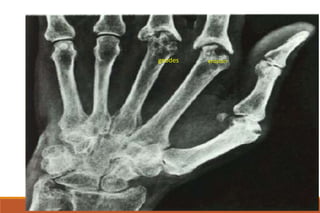

RHEUMATOID ARTHRITIS

X-rays

◦ The earliest changes occur in the wrist or feet and consist of soft

tissue swelling and juxta-articular demineralization.

◦ Later, diagnostic changes consisting of joint space narrowing and

erosions develop. The erosions are first seen at the ulnar styloid

and at the juxta-articular margin, where the bony surface is not

protected by cartilage.

Juxta-articular osteoporosis

Bony erosions

erosion

geodes

marginal erosions

narrow joint space